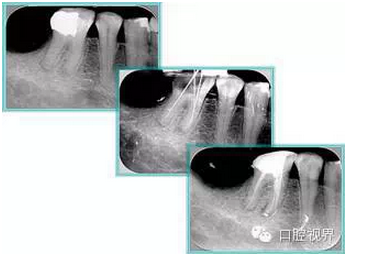

( 3 )塑化 + 根充。

如圖為塑化加根充處理后牙齒 X 線片。

器械已經(jīng)預(yù)彎但仍阻力很大,推測根管彎曲呈“V”字型,應(yīng)如何處理?更換器械常規(guī)探查時根管應(yīng)在根尖1/3做小的預(yù)彎。器械到達根尖1/3時不要強力擰入,選擇左右擺動旋轉(zhuǎn),保證沿原始通路下探。根管彎曲呈“V”字型時器械即使左右擺動旋轉(zhuǎn)也無法插入,還可能造成臺階。此時應(yīng)更換更為細小的器械插入,因為更為細小的器械依從性更好。到達工作長度后用測量儀測量,取出時觀察器械彎曲程度。

解決方法: 1 )徹底去除根充物。 2 )使用塑化液溶解劑或 EDTA ,保持根管濕潤。

3 )通常先使用 15#K 銼,將銼的根尖 3 -4mm 處預(yù)彎,若尚未到達工作長度而出現(xiàn)銼的螺紋擰緊,應(yīng)立即換用小號的銼,如 10# 、8# 的K銼。 4 )使用 H銼銼平臺階。 5 )反復(fù)經(jīng)常的沖洗根管。

注意:沒有病變,叩疼陰性,沒有陽性體征,X 線片示不理想的根管治療狀態(tài),根尖沒有異常,根周膜影像正常時,表明療效較好,不要強行治療。文獻報道根管治療再治療成功率 50% ,進行再次治療應(yīng)慎重。